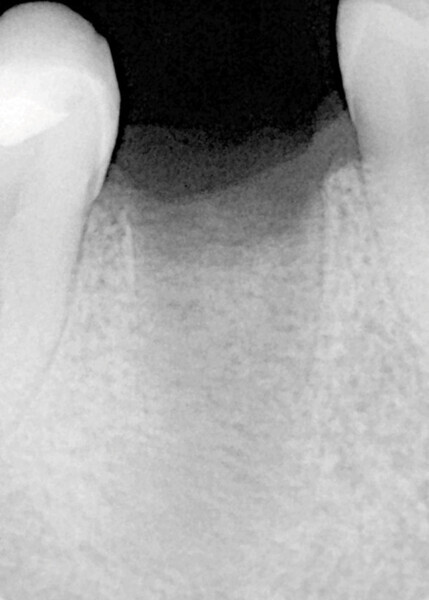

Fig. 1

Le patient, âgé de 27 ans, présentait un kyste apical ainsi qu’une atteinte de la furcation de la 46 ne nous permettant pas le retraitement et l’exérèse kystique. La décision de l’avulsion a donc été prise, en vue de la pose d’un implant (Fig. 1).